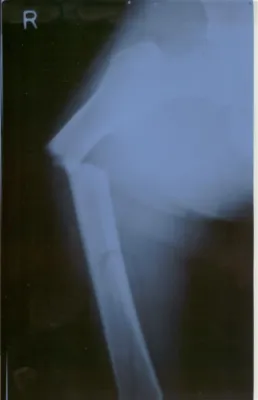

Prostaglandine sind die Entzündungs- und Fieberbotenstoffe des Körpers. In der Folge kommt es also direkt am Knochen zu einer nicht-bakteriellen Entzündungsreaktion, die in der Regel mit Verdickungen des Knochens und Wassereinlagerungen einhergeht. In ausgeprägten Fällen kann auch der Eindruck entstehen, es handle sich bei diesen Verdickungen um Knochentumore, wie Girschick an zwei Fallbeispielen zeigen konnte. Zugleich wird die Knochenstruktur geschwächt, und es kann zu Brüchen kommen.